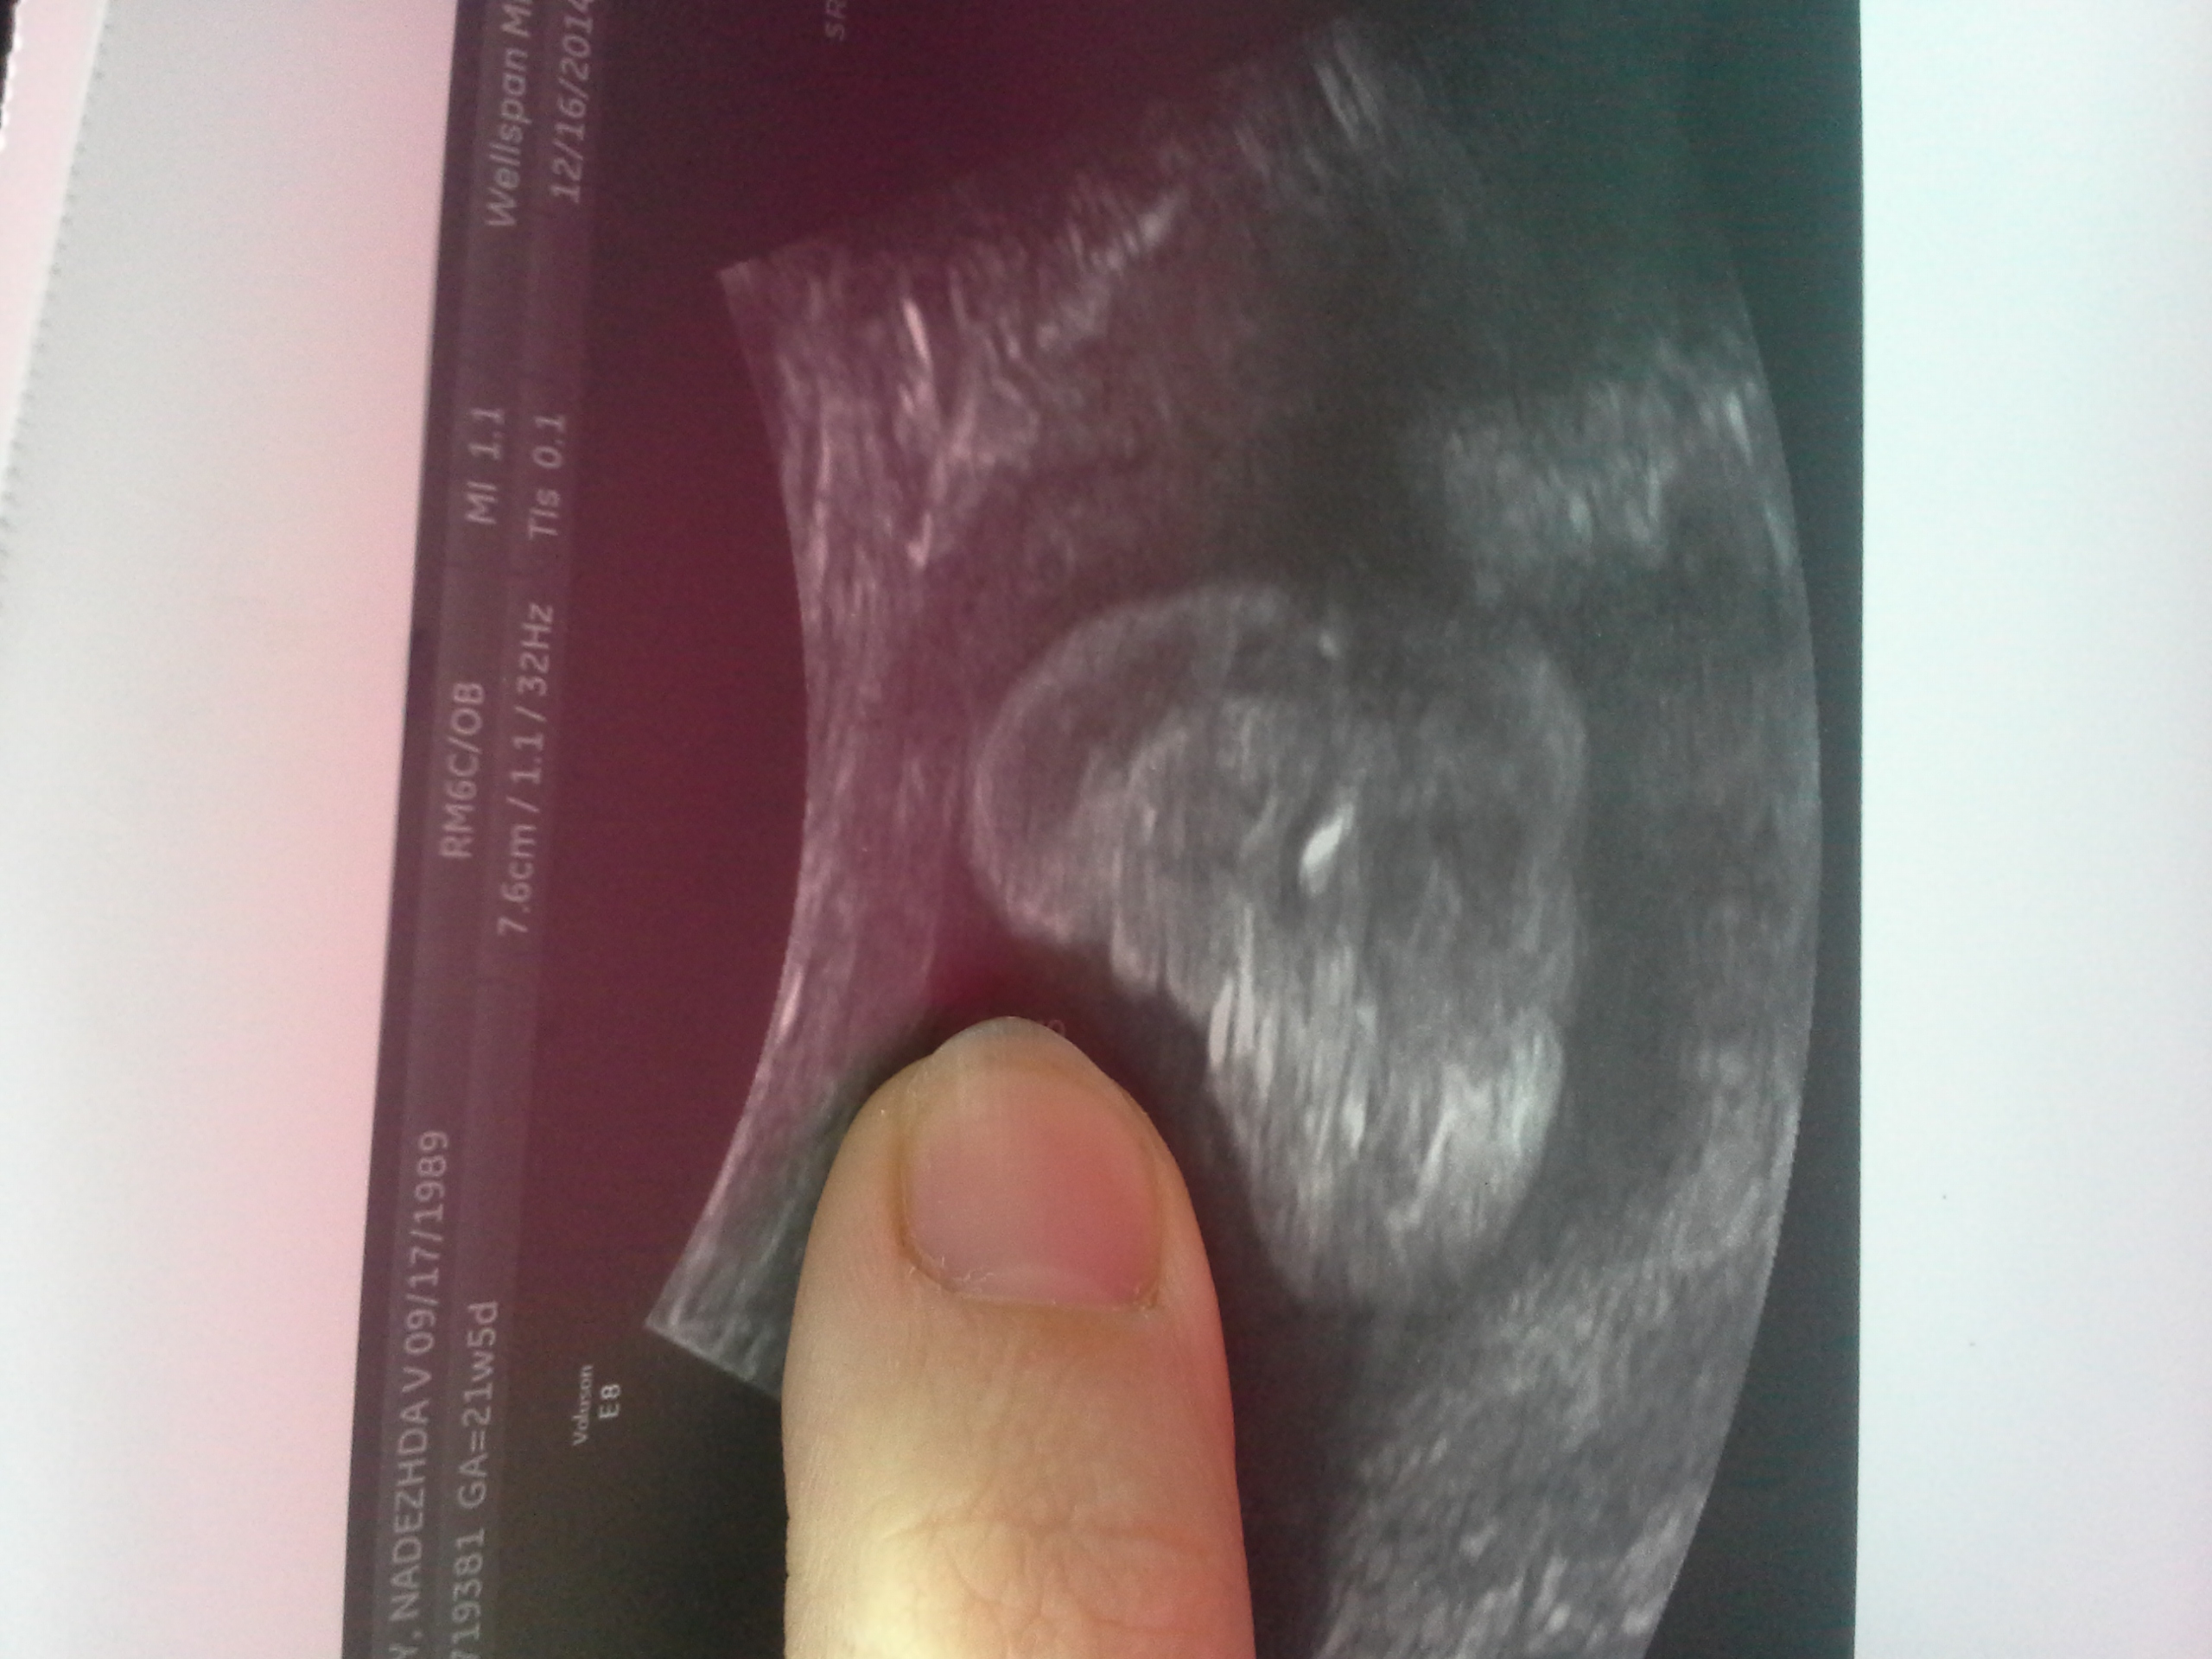

Boy or Girl? Confused...21 weeks